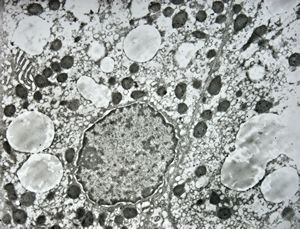

M,2y. | normal hepatocyte